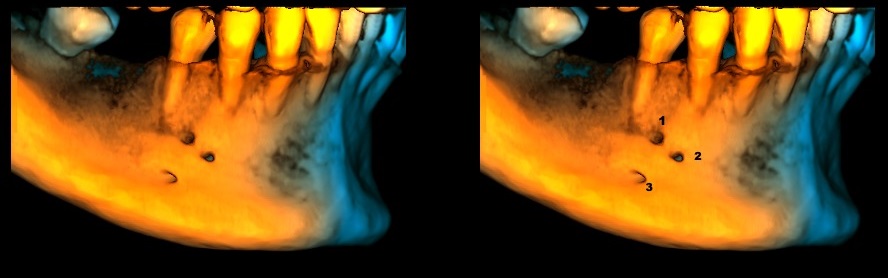

En la reconstrucción 3D se representa la presencia de foramen mentoneano junto a los dos foramenes accesorios de lado derecho (Figura 3).

RECONSTRUCCIÓN 3D